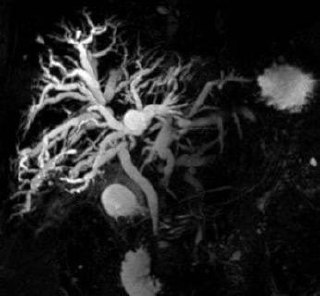

И тогда , скорее всего, пациент попадет на МР- холангиопанкреатографию.

Первичный склерозирующий холангит! Его относят к орфанным заболеваниям, но все же врачу-гастроэнтерологу ведущему пациентов с Болезнью Крона или Язвенного колита не стоит забывать, об этой патологии. Так как она часто встречается с ВЗК. На узи многие специалисты могут не заметить существенных изменений в протоках желчевыводящих путей. Что происходит в данном случае? Антитела атакуют желчные протоки, вследствие чего образовывается воспаление в них, а в дальнейшем воспаление заканчивается рубцеванием, рубцевание заканчивается сужением промежутков этих самих протоков. А значит🤔, нарушается желчеотток. Со временем повышается билирубин, если сужение стало значительным. Могут образовываться камни в желчных протоках. На первых порах, пациента ничего не беспокоит, кроме повышения ЩФ, ГГТ в анализах. Возможно диарея, боль в правом подреберье, но когда билирубин сильно повышается появляется желтушность и зуд кожи… И тогда , скорее всего, пациент попадет на МР- холангиопанкреатографию.